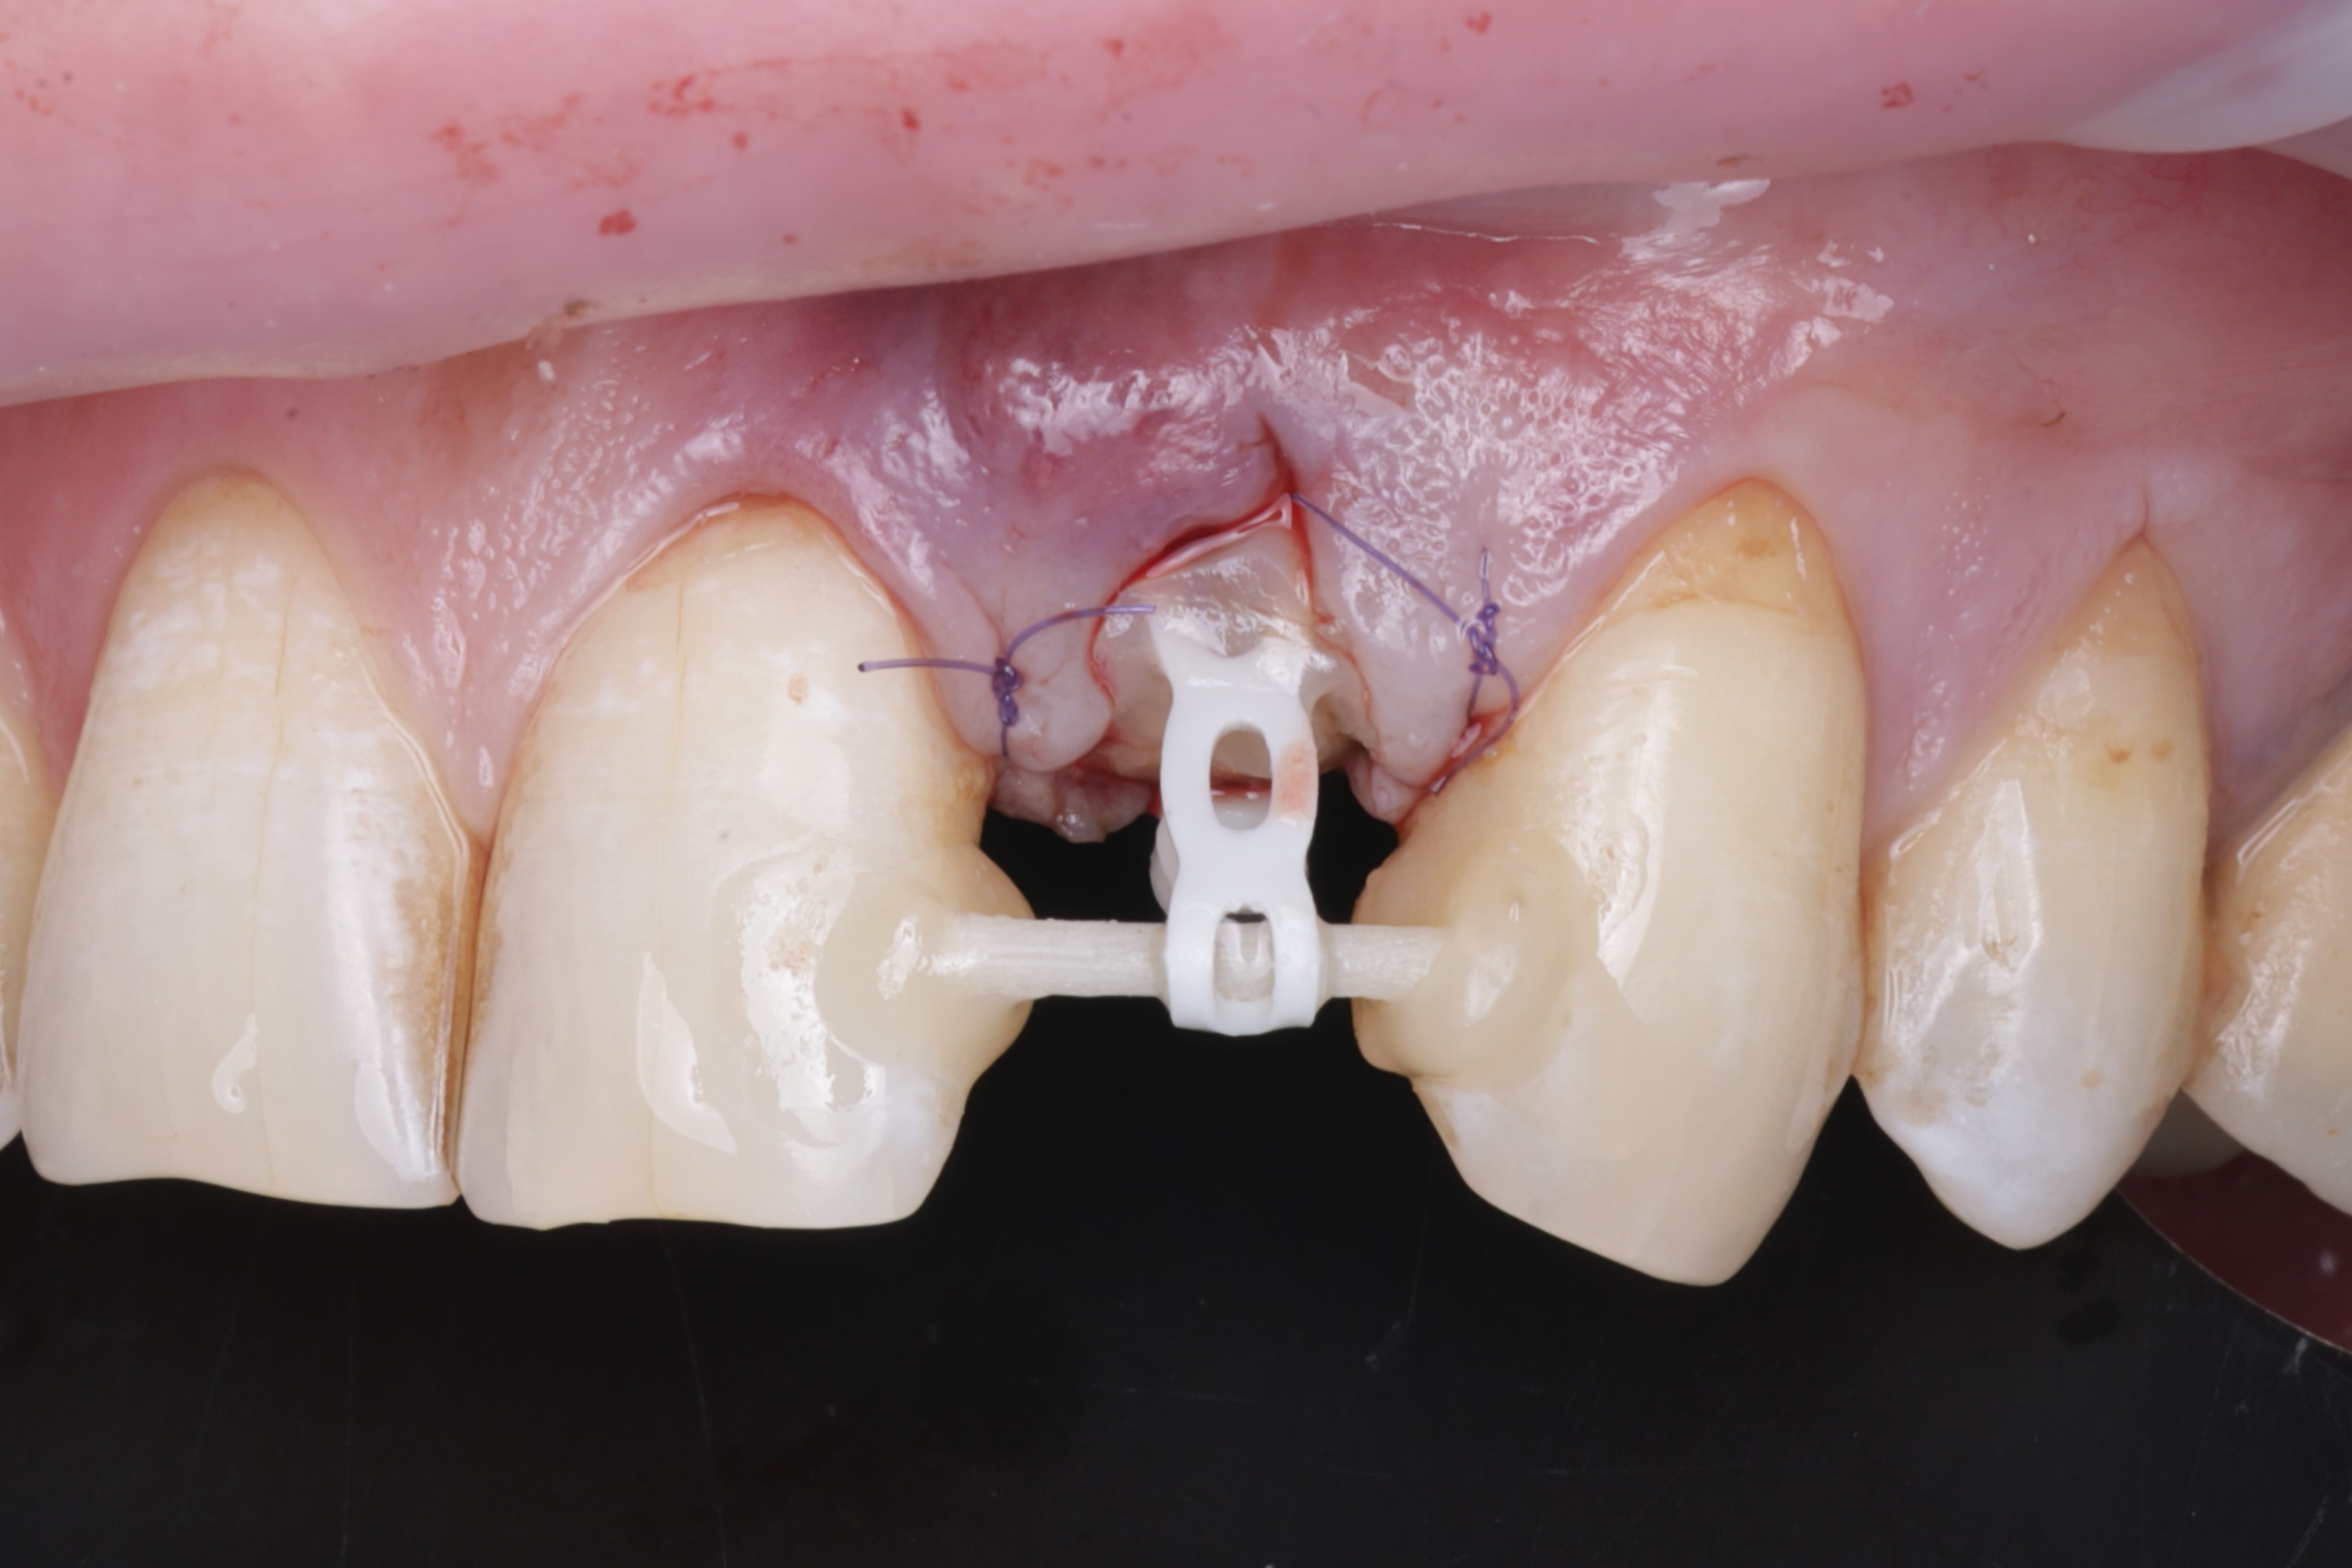

Зафиксирован стекловолоконный штифт и ортодонтическая тяга для вытяжения зуба.